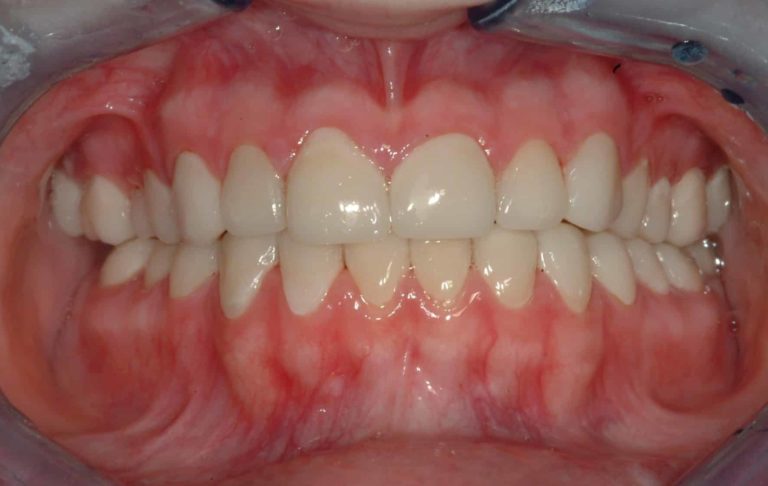

Before & After Gallery